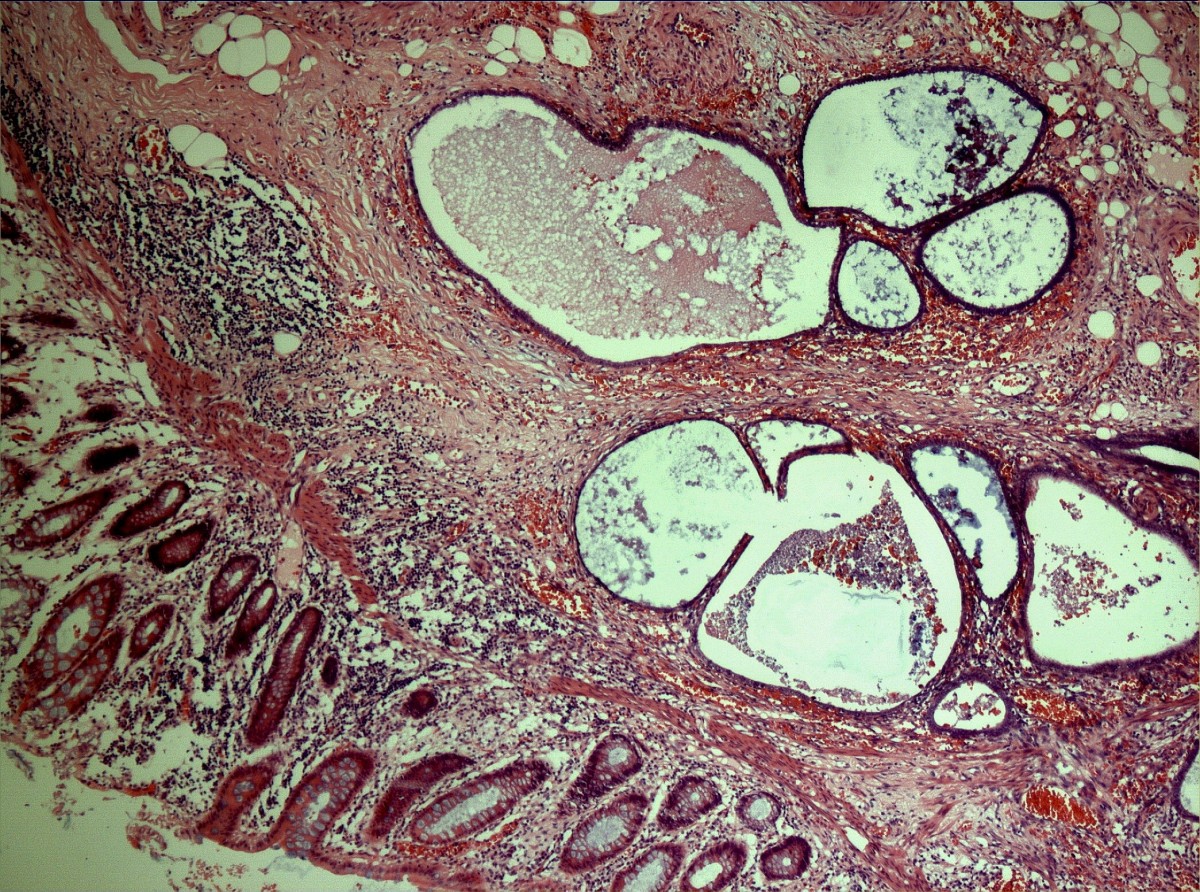

From www.pathologyatlas.ca

Endometriosis involving the appendix Atlas of Pathology Endo On Appendix endometriosis of the appendix is uncommon. acute appendicitis is the most common surgical diagnosis of abdominal pain in the right lower quadrant [1]. we report a case of endometriosis of the appendix and review the literature regarding endometriosis of. In rare cases, endometriosis spreads to the appendix. Its clinical presentation varies from asymptomatic to acute abdominal. . Endo On Appendix.

From www.researchgate.net

Histopathological examination (a) Gross examination of the appendectomy Endo On Appendix endometriosis of the appendix is uncommon. Its clinical presentation varies from asymptomatic to acute abdominal. we report a case of endometriosis of the appendix and review the literature regarding endometriosis of. acute appendicitis is the most common surgical diagnosis of abdominal pain in the right lower quadrant [1]. sometimes it can even spread outside of the. Endo On Appendix.